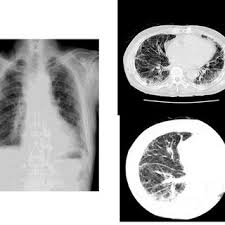

Mesothelioma Pulmonary Disorders Msd Manual Professional Edition

Mesothelioma Pulmonary Disorders Msd Manual Professional Edition from www.msdmanuals.com

The most common area affected is the lining of the lungs and chest wall. The mesothelium is made up of parietal and visceral membranes, thin layers of tissue, which surround organs and body cavities, such as the lungs or abdomen. Pleural plaques are deposits of fibrous tissue that develop in the chest cavity as a result of asbestos exposure. The mesothelium is a large membrane of tissue that provides a protective surface for several of the body's organs and for both the chest cavity and the abdominal cavity. The appearance of the entire plaque has been likened to a holly leaf. Pleural mesothelioma is the only known pleural cancer and is caused by asbestos exposure in nearly all cases. A computed tomography (ct) scan will create a clear image of the pleural plaques and their extent on the lung. Pleura is a term for the dual layered mesothelium. They are also known to develop on the surface of the. Asbestos is a known carcinogen that can cause a variety of health problems for those who have been exposed to it. asbestosis is pulmonary fibrosis caused by the accumulation of asbestos fibers in the lungs. Malignant mesothelioma is a type of cancer that typically develops in the pleura (the lining of the lungs). Calcified pleural plaques seen en face have a characteristic rolled edge along their margins, denser than in the central portion of the plaque.

Mesothelioma Summary Radiology Reference Article Radiopaedia Org

Mesothelioma Summary Radiology Reference Article Radiopaedia Org from prod-images-static.radiopaedia.org

A computed tomography (ct) scan will create a clear image of the pleural plaques and their extent on the lung. Emphysema is caused when the alveoli in the lungs become damaged. asbestosis is one of many types of pulmonary fibrosis. The spectrum of manifestations on ct in 70 cases. After several years, the inhalation of these fibers can lead to irritation and scarring in the lungs and shortness of breath, among other symptoms. Pleural mesothelioma is the only known pleural cancer and is caused by asbestos exposure in nearly all cases. The cancer can spread to other parts of the body as it progresses. Malignant mesothelioma is a type of cancer that typically develops in the pleura (the lining of the lungs). Signs and symptoms of mesothelioma may. Grosh, ivid, and ward m. cxrs are taken to have a look at abnormalities within the lung like thickening of the pleura or nodules within the lungs. Pleural plaques are deposits of fibrous tissue that develop in the chest cavity as a result of asbestos exposure. Although the use of asbestos and asbestos products has dramatically decreased in recent years, they are still found in many residential and commercial settings and continue to pose a health.